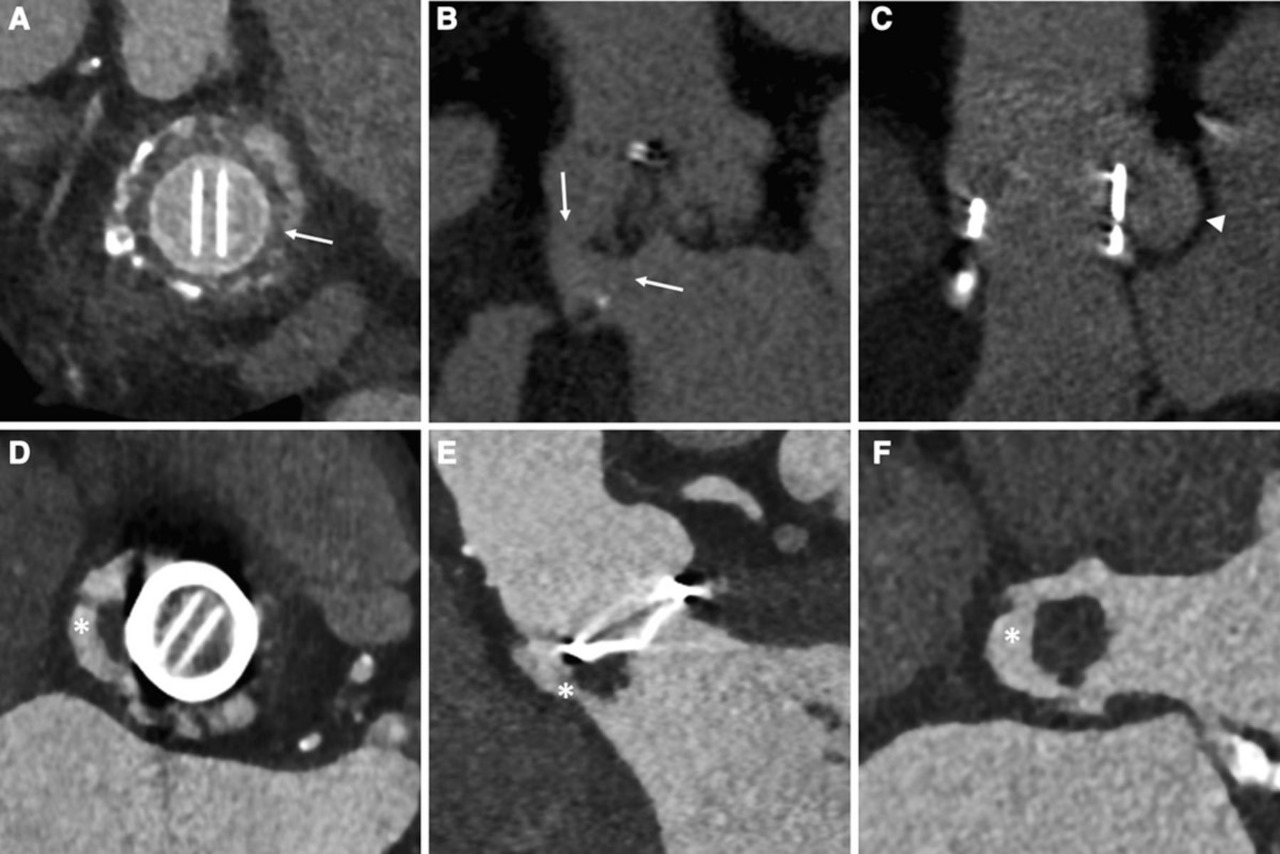

Cinefluoroscopy of the prosthetic aortic valve and transoesophageal... Download Scientific Prosthetic Valve Guidelines Echo Thus, the cardiac history plays a major role in the echocardiographic evaluation by documenting the type and size of the inserted valve or conduit. The transthoracic approach is complemented with two. This document offers a review of echocardiographic and doppler techniques used in the assessment of prosthetic valves and provides recommendations and general guidelines for the. In clinical practice, a. Prosthetic Valve Guidelines Echo.